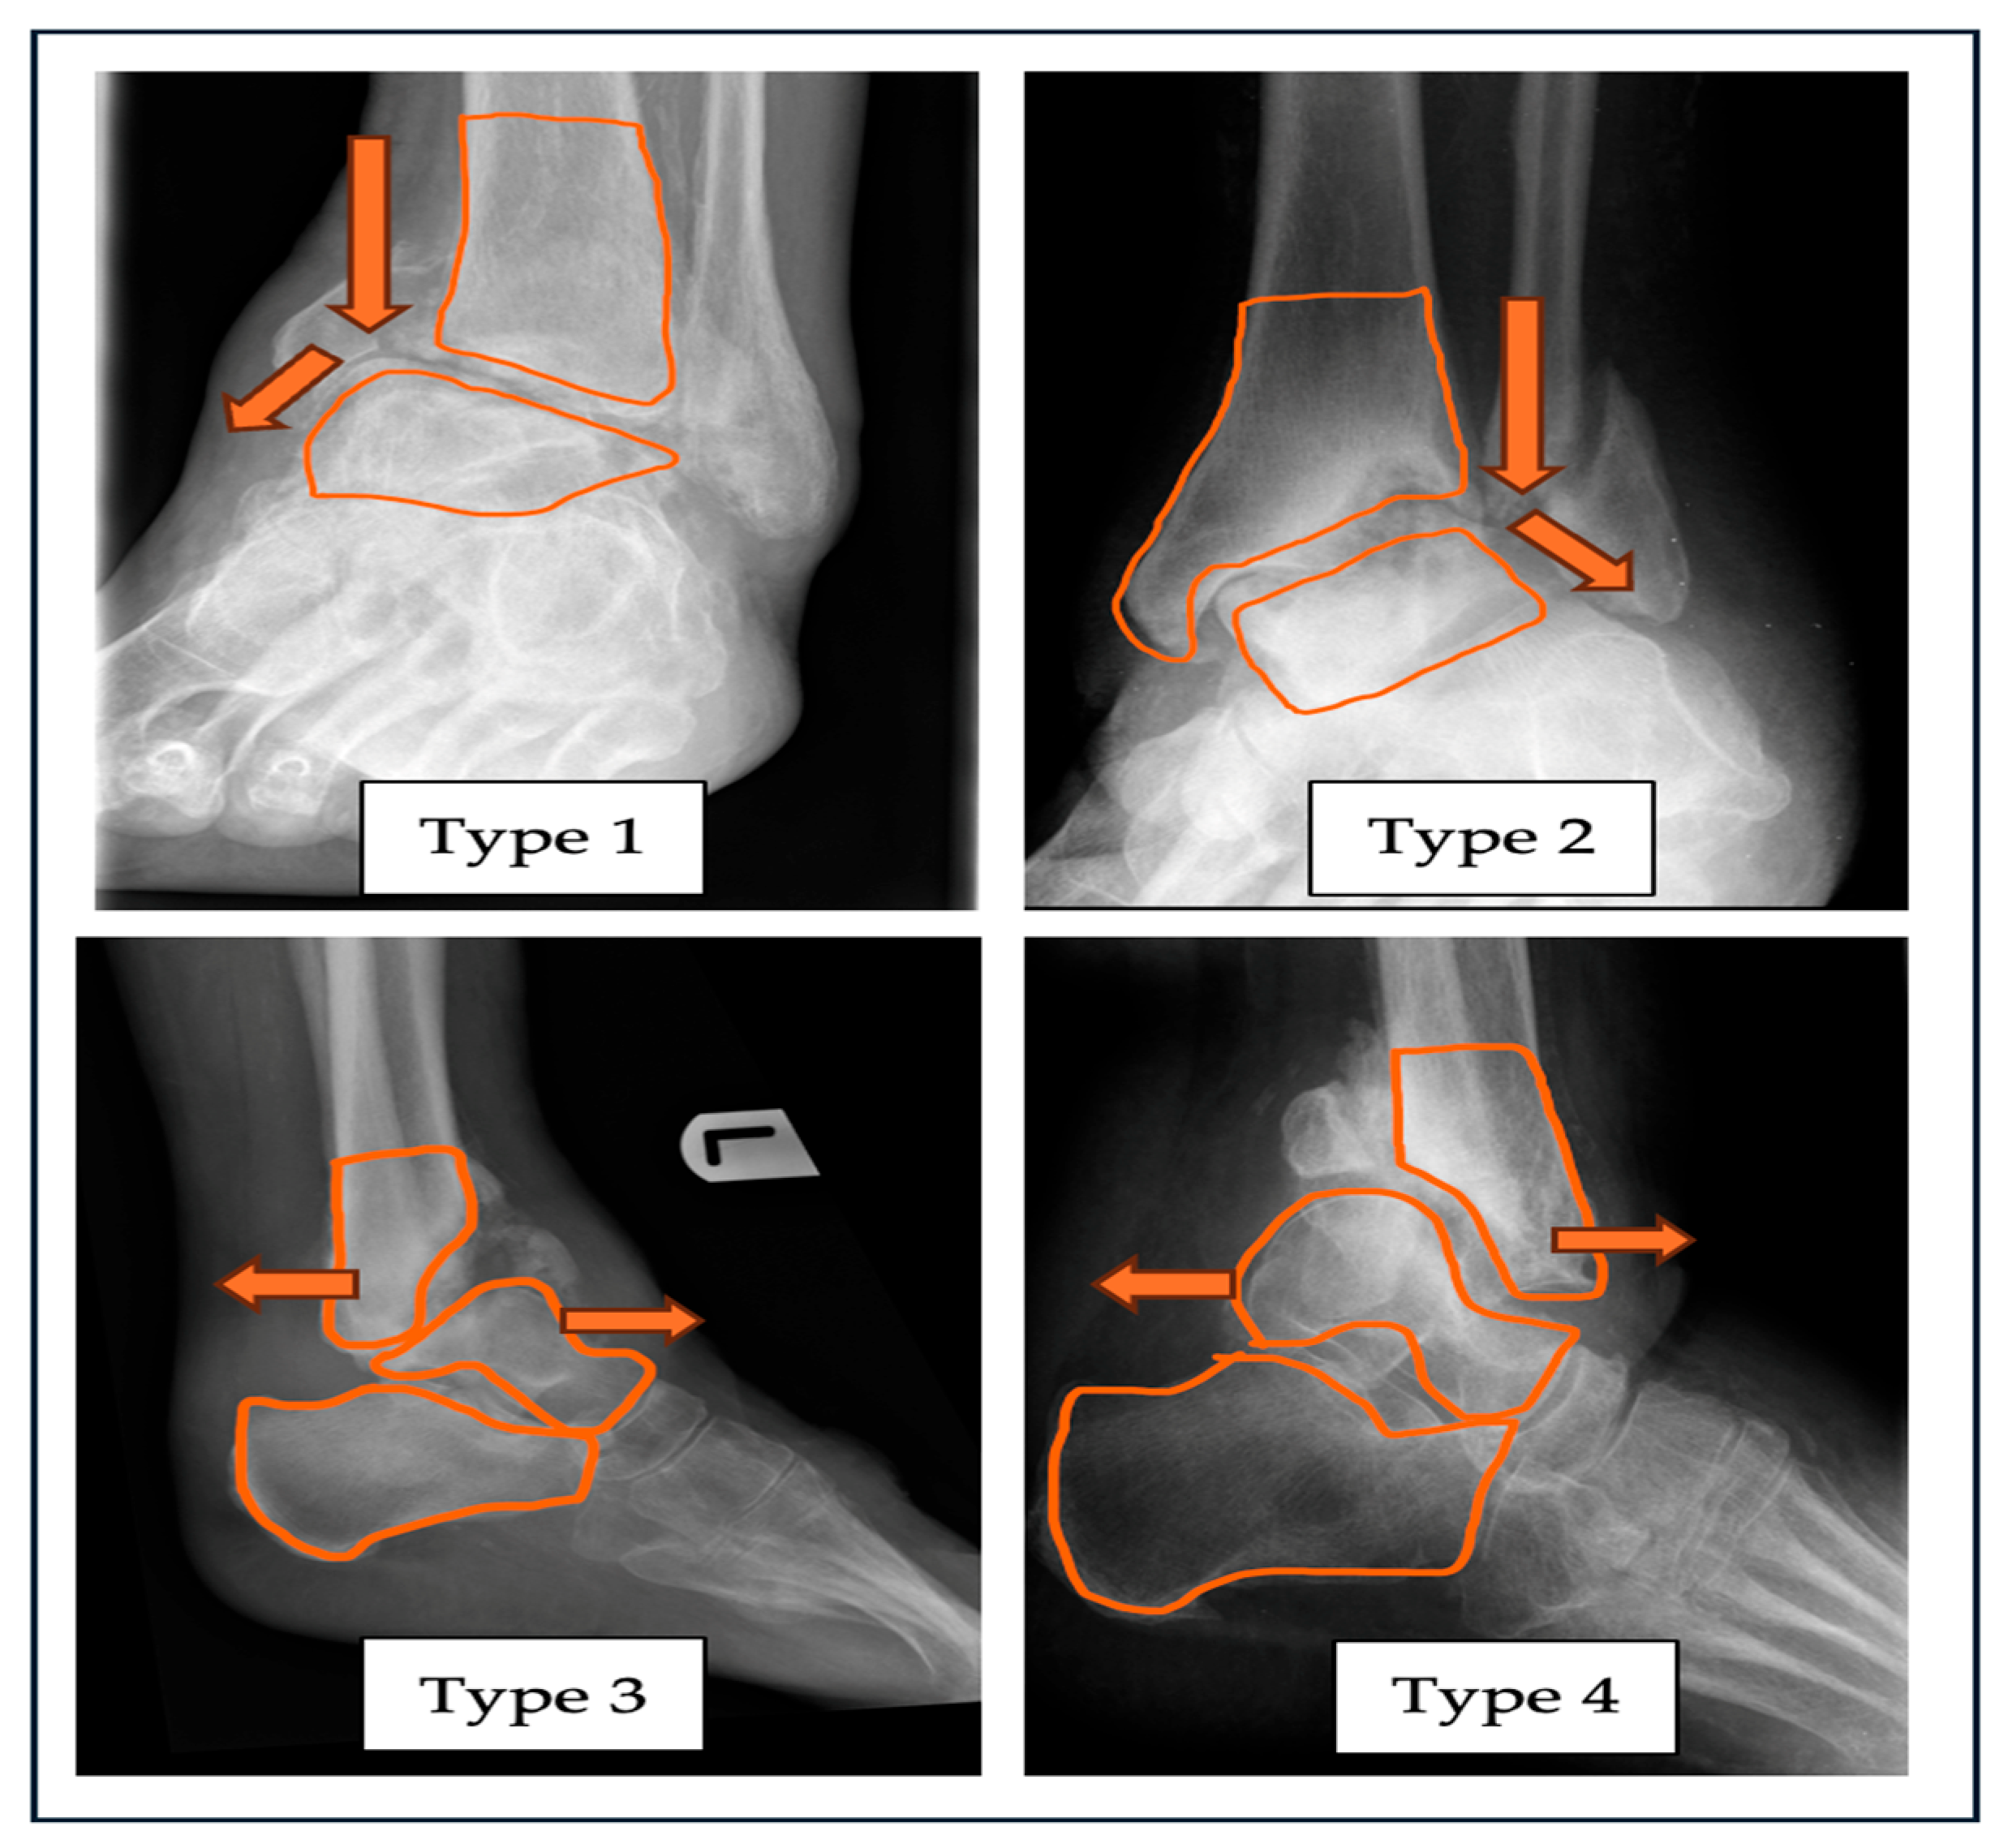

In the abbreviation, “A” stands for alignment of the ankle joint in the coronal varus (Type 1) or valgus (Type 2) deformity. Sagittal plane deformity can be classified with the plane of either anterior (Type 3) or posterior (Type 4) angulation of the involved joint. If the diagnosis of ankle Charcot is confirmed, in the absence of any alignment deformity, it can be classified as Type N (neutral). A combined deformity with subluxation and/or dislocation, which refers to a multiplanar deformity, can be classified as Type 5.

Figure 1. Radiograph with superimposed illustrations of four different types of alignment deformities related to ankle CN: Type 1—varus, Type 2—valgus, Type 3—anterior angulation, Type 4—posterior angulation of the ankle joint. .